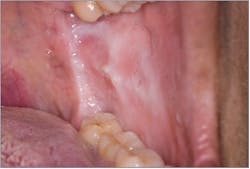

Leukoedema

Leukoedema (figure 3) presents as a diffuse, milk-white, opalescent lesion on the bilateral buccal mucosa that disappears when the mucosa is stretched. It is most common in the African American population, with reports of patients having this feature since early childhood. Consequently, it is considered a variation of normal.4 Dental hygienists can distinguish this lesion more easily with findings from the clinical exam and information from the patient’s dental history.